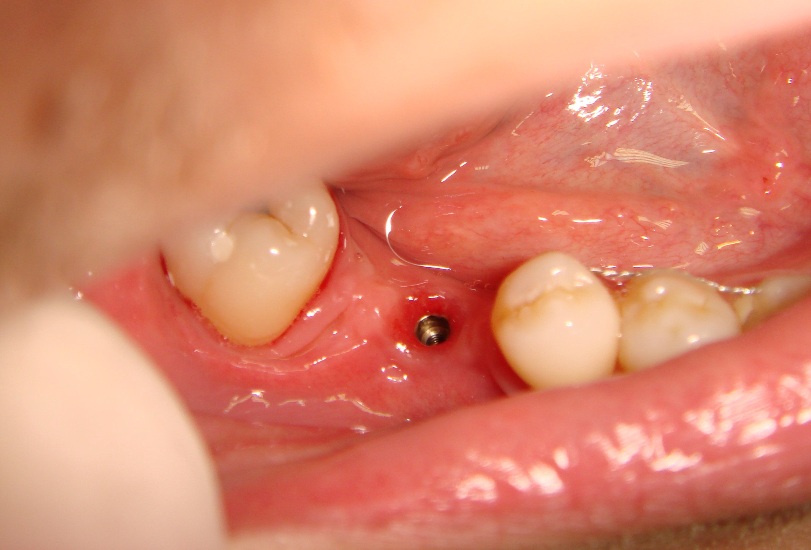

Photo 3. Oral cavity of the same patient: state of alveolar process, dentition and mucous membrane in the area of mandibular dentition defect at site of 46th tooth after implantation and formation of mucous membrane.